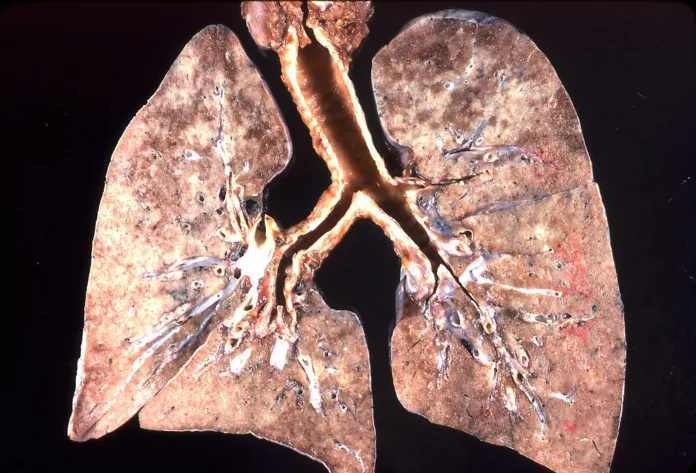

Люди в возрасте от 50 до 75 лет, которые не менее 25 лет курили или курят около пачки сигарет в день, с апреля могут раз в год проходить бесплатную компьютерную томографию лёгких. Как сообщает MDR, эту услугу ввели для ранней диагностики рака, который на поздних стадиях часто оказывается смертельным. Цель — выявлять болезнь на излечимом этапе и спасать жизни.

Расходы на обследование покрывают больничные кассы, которые рассчитывают таким образом сэкономить на дорогом лечении запущенных случаев. Хотя само обследование несёт небольшой риск из-за лучевой нагрузки, эксперты считают, что для курильщиков польза от ранней диагностики значительно превышает возможный вред.